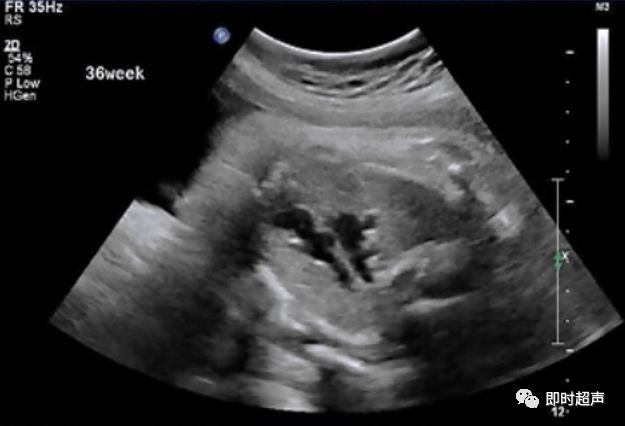

探到胎儿四腔心后,探头稍向胎儿头侧偏移即可显示三血管-气管切面,正常三血管-气管平面从左到右依次显示:肺动脉、主动脉弓、气管、上腔静脉。

胎儿三血管气管切面

三血管-气管切面的观察内容

- 从左到右依次是肺动脉、主动脉弓和上腔静脉

- 内径从左到右依次递减

- 主动脉弓位于气管的左侧

- 肺动脉和主动脉弓血流都流向脊柱,呈后向血流

- 肺动脉经动脉导管与主动脉弓共同汇入降主动脉